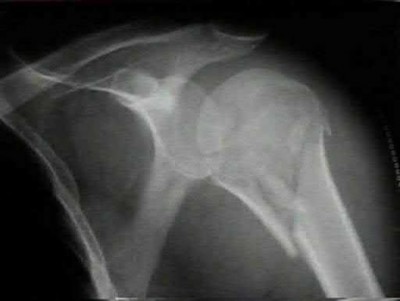

A 12-year-old obese boy presents with vague left thigh and knee pain. He is diagnosed with a Slipped Capital Femoral Epiphysis (SCFE) as seen in similar clinical scenarios.

During percutaneous in-situ fixation, unrecognized penetration of the guide wire into the hip joint occurs. What is the most likely specific complication resulting from this technical error?

Chondrolysis is a severe complication of SCFE characterized by rapid destruction of the articular cartilage. While it can occur idiopathically, its most established iatrogenic cause is unrecognized intra-articular hardware penetration. The 'approach-withdraw' fluoroscopic technique is required during pinning to assure pins are entirely intraosseous. Avascular necrosis (AVN) is usually due to damage to the epiphyseal blood supply (retinacular vessels) secondary to the initial displacement, forceful closed reduction, or posterosuperior pin placement.